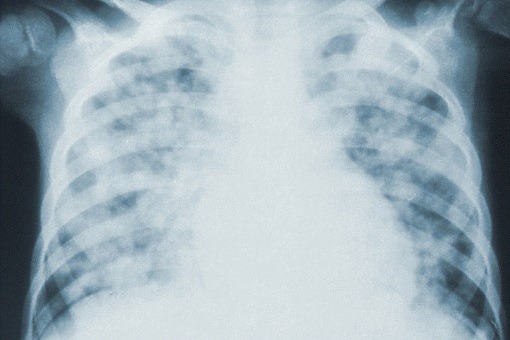

Sildenafil i pirfenidon u pacjentów z idiopatycznym włóknienie płuc i ryzykiem nadciśnienia płucnego

Na łamach Lancet Respiratory Medicine ukazały się wyniki badania klinicznego fazy 2B, w którym do terapii pacjentów z idiopatycznym włóknieniem płuc z ryzykiem nadciśnienia płucnego dodano sildenafil.